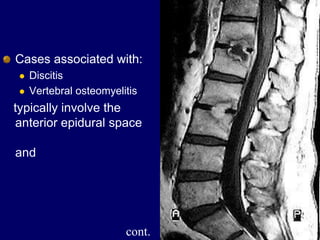

Cases associated with:

 Discitis

 Vertebral osteomyelitis

typically involve the

anterior epidural space

and

cont.